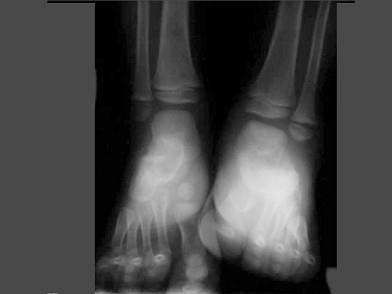

女,5岁,左踝疼痛,请结合图像,选出最可能的诊断 ( )A、风湿性关节炎B、痛风C、退行性骨关节病D、神经性关节病E、创伤性关节炎

问题 女,5岁,左踝疼痛,请结合图像,选出最可能的诊断 ( )

选项 A、风湿性关节炎 B、痛风 C、退行性骨关节病 D、神经性关节病 E、创伤性关节炎

答案 D